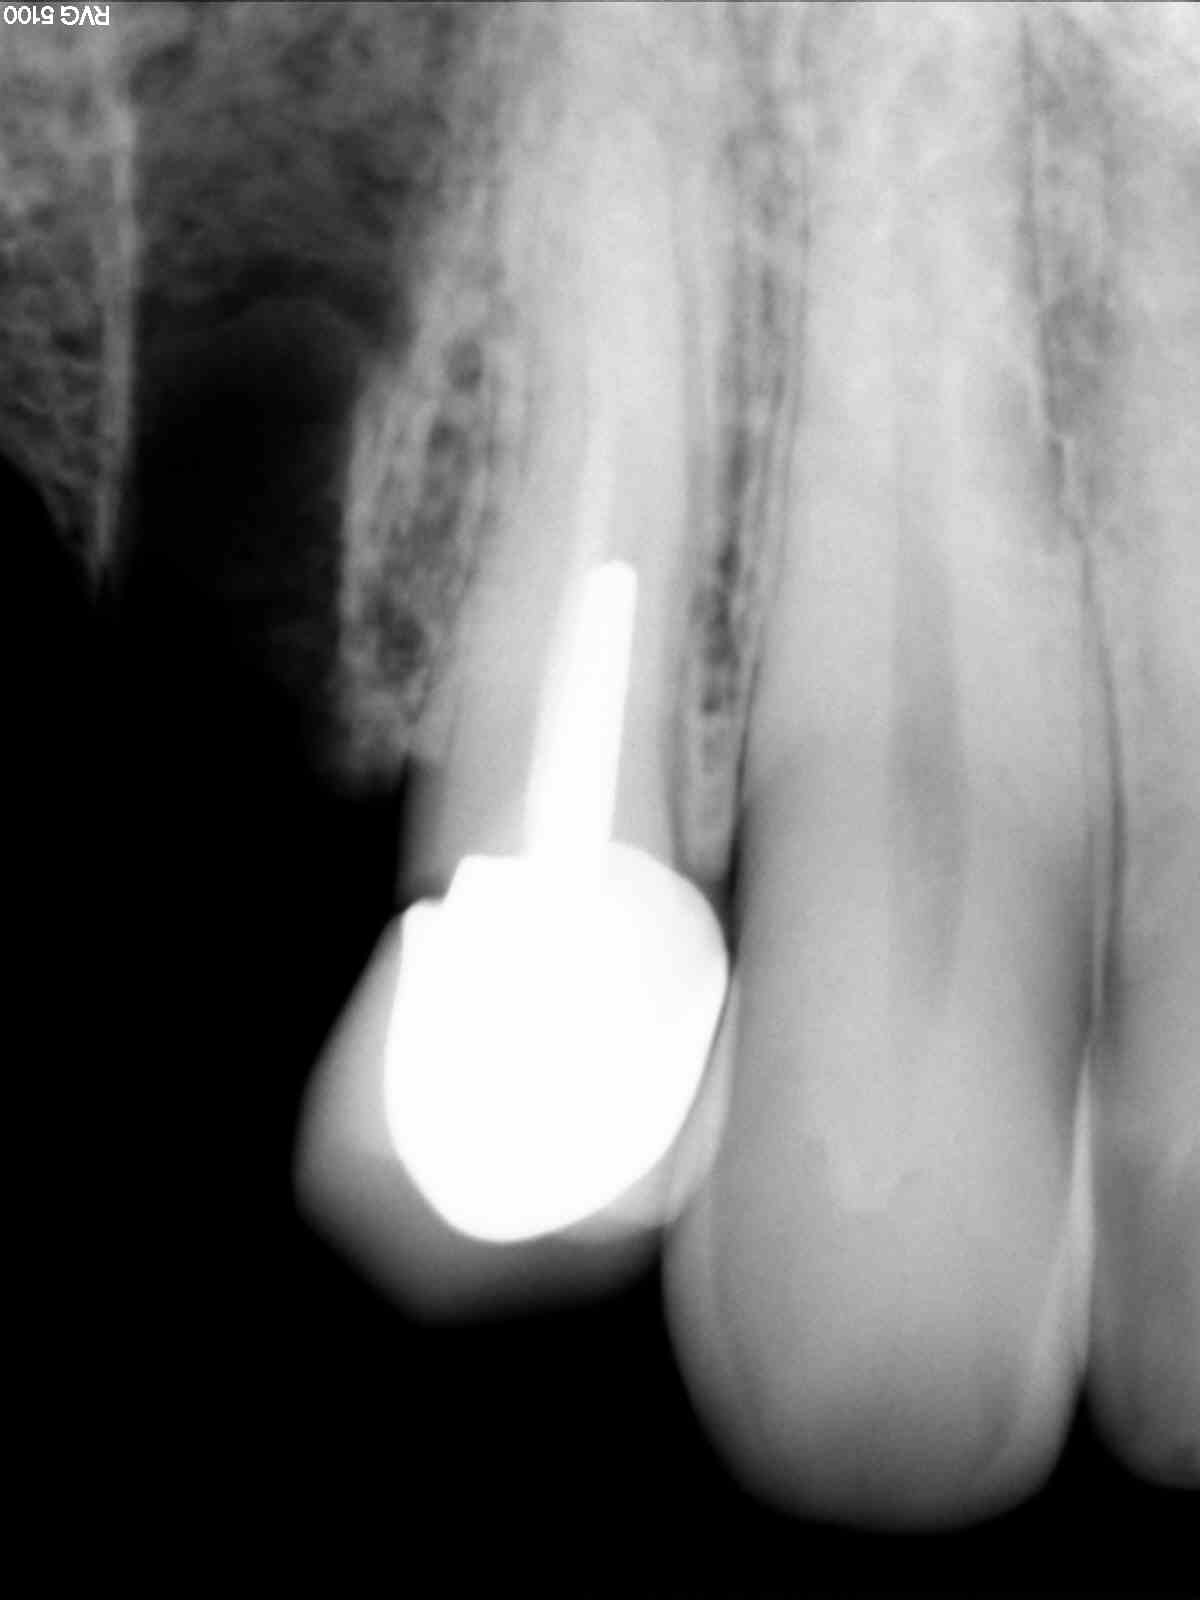

Radios1 dxb8my - Eugenol

Radios2 kprrcu - Eugenol

Radios3 auio0x - Eugenol

Radios4 pfsefa - Eugenol

Radios5 uwurgt - Eugenol

Radios6 ycayfo - Eugenol

Des inlay core... Des endos moisies... C est un français.

Ah ? C'est un français il a des inlay cores et des endos pourries. Ca réduit considérablement les recherches. -))))

maladie dentaire diffuse + antécédent de choc (11 racine fracturée)